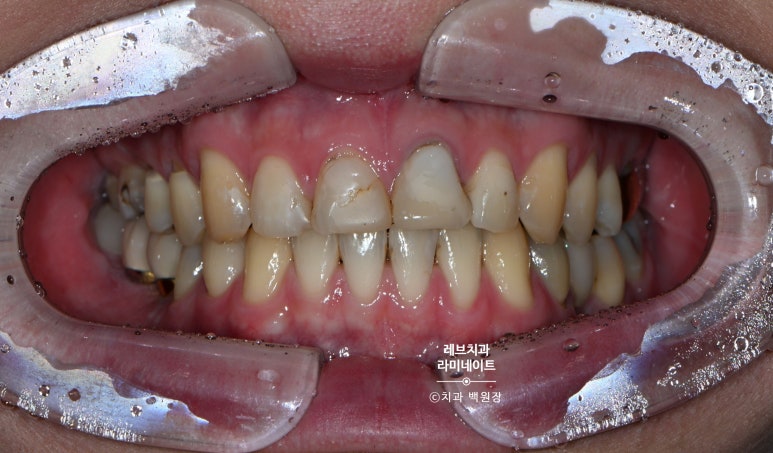

오늘 소개해드릴 환자분은 앞니의 충치 때문에 이미 여러번 레진치료를 받았던 환자분이었습니다.

저희 병원에 내원한 유튜버셨는데요, 앞니가 특히 레진으로 덕지덕지 치료되어 있는 것을 보실 수 있습니다.

치아를 보존하는 것. 물론 중요합니다만... 레진 치료 위에 또 레진을 붙이고 붙이고... 이제는 치아의 절반은 레진이었고 변색되는 치아에 지쳐있는 분이셨어요.

깔끔한 남자분의 외모와는 달리 깔끔해보이지 않는 치아였습니다.

그래서 웃음도 마음대로 못짓는 안타까운 상황...